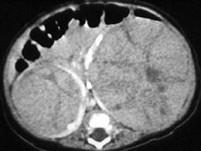

问题 男,2岁,触及腹部包块,未及肿大淋巴结,请根据所示图像,选择最可能诊断 ( )

选项 A、双侧肾癌 B、双肾神经母细胞瘤 C、双肾转移瘤 D、双侧肾母细胞瘤(Wilms瘤) E、双肾淋巴瘤

答案 D